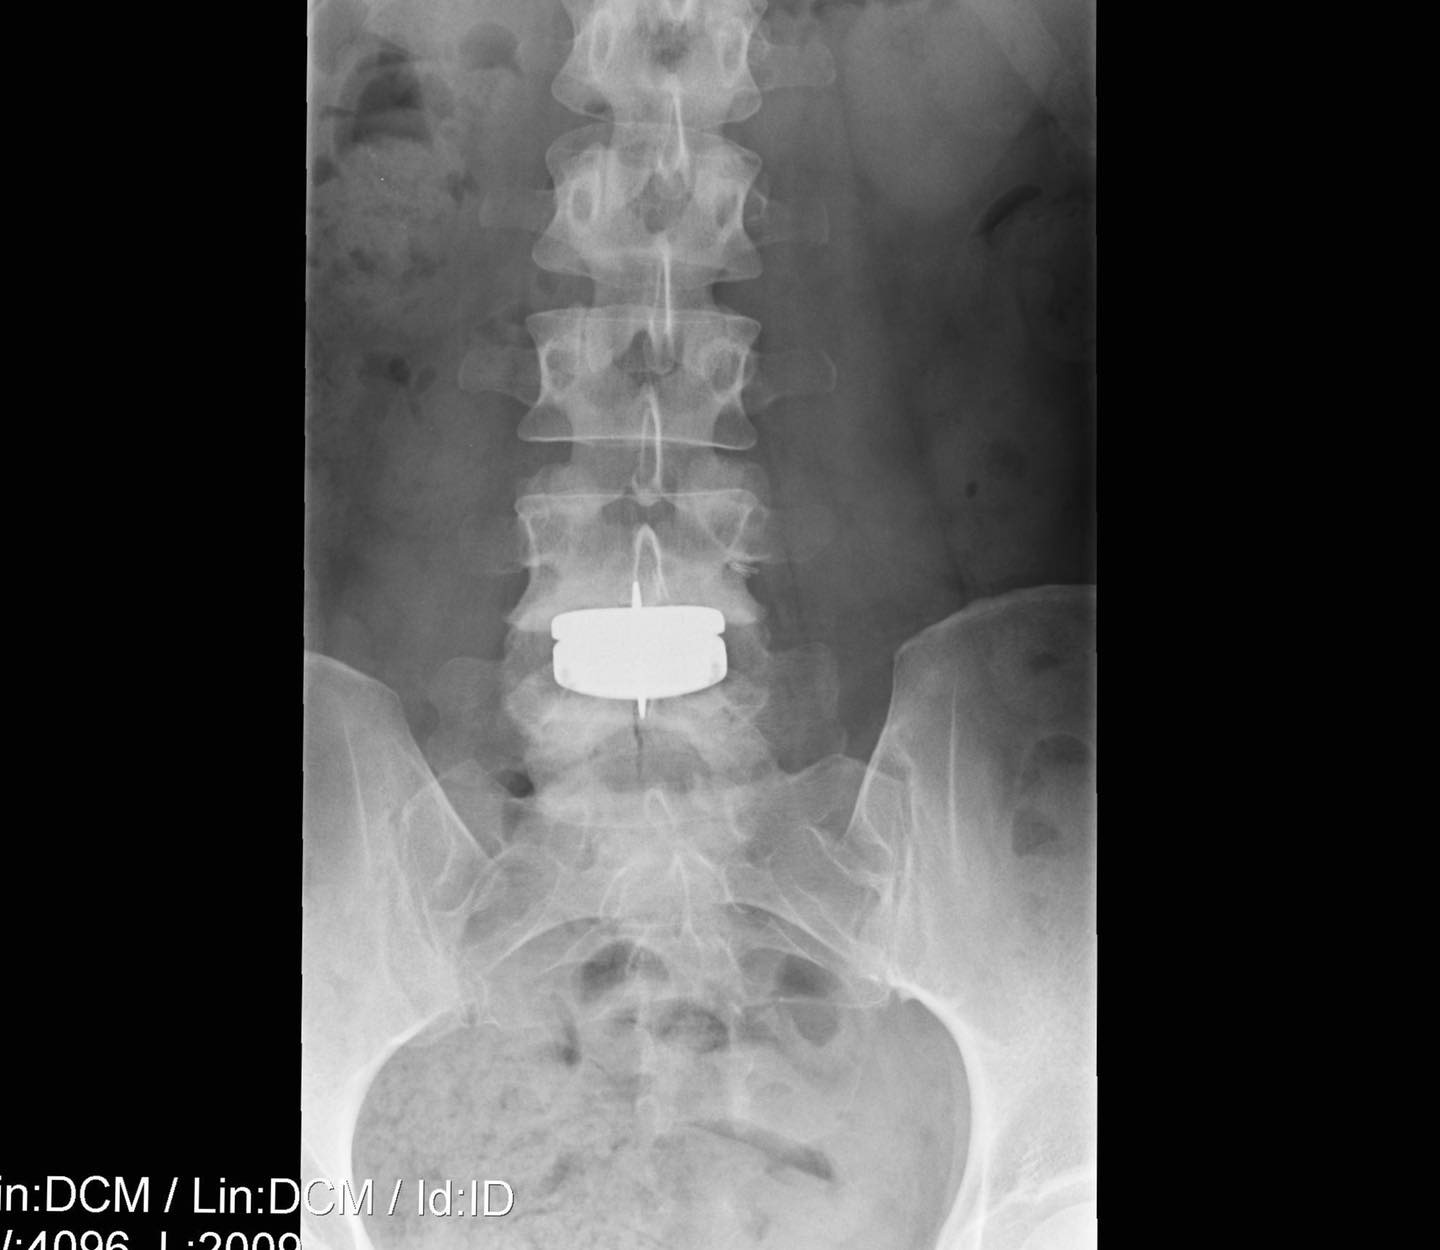

jennifer valdez bio, age, education, family, husband, cbs46, net worth, salary. jennifer valdez is the chief meteorologist at cbs46 in atlanta, georgia. She has a bachelor's degree in telecommunications and a master's degree in. Jennifer valdez is an american meteorologist working as a chief meteorologist, weather anchor, and reporter at cbs 46 based in atlanta. In 2020, jennifer valdez underwent major back surgery, opting for artificial disc replacement to address a deteriorating disk in her lower back. “i’ll have a good day, then feel awful for three,” said valdez, 39, who joined the station. jennifer valdez’s weight loss is likely the result of health challenges. three weeks after major back surgery, cbs46 chief meteorologist jennifer valdez is still in pain. jennifer valdez weight loss drawing from her photos, it is evident that jennifer has lost a significant amount of weight which could be from workouts or a change in eating habits. However, she has not disclosed any information to the public regarding her weight loss.